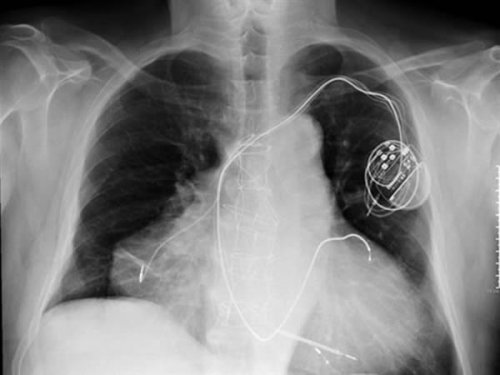

Երբ Վերոնայի հիվանդանոց ժամանեց մի տղամարդ սրտանոթային խնդիրների ախտանիշներով, դա ոչ մի զարմանք չառաջացրեց:

Բժիշկները կարծում էին, թե սրտի կաթված է տեղի ունեցել, սակայն նրանք փոխեցին իրենց կարծիքը՝ հիվանդին ավելի մանրամասն հետազոտելուց հետո: Պարզվեց, հիվանդը ծնվել էր երկու սրտով: Երկրորդ սիրտը առաջինի վրա հայտնվել էր բժշկական գործողություններ անցկացնելուց հետո:

Այդ գործողությունն իրականացվում է վնասված օրգանի հետ առողջ օրգանը համատեղելու համար: Այս դեպքում մեծ ռիսկ կա, որ կարող է իրարից անկախ սրտային երկու ռիթմեր ձևավորվեն և, ամենայն հավանականությամբ, հենց դա էլ տեղի էր ունեցել իտալացու հետ:

Բժիշկների ճշգրիտ գործողությունների արդյունքում իտալացու երկու սրտերը կրկին աշխատեցին, և հիմա նա իրենց շատ լավ է զգում: